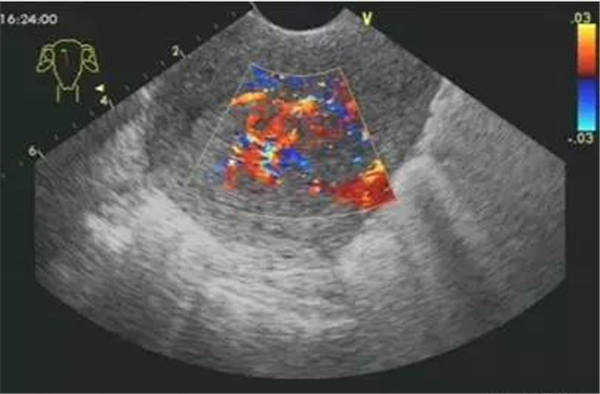

血栓

血栓是血栓性肺栓塞最典型的特征,位于右房或右室中的血栓可形態各異,而位于肺動脈內時則常表現為大塊血栓,從主干延續至一側或雙側肺動脈分支。右肺動脈主干血栓易于顯示,左肺動脈因顯示較短,血栓不易顯示。此外,需注意將血栓與右心系統腫瘤相鑒別。

右心血栓 肺動脈血栓